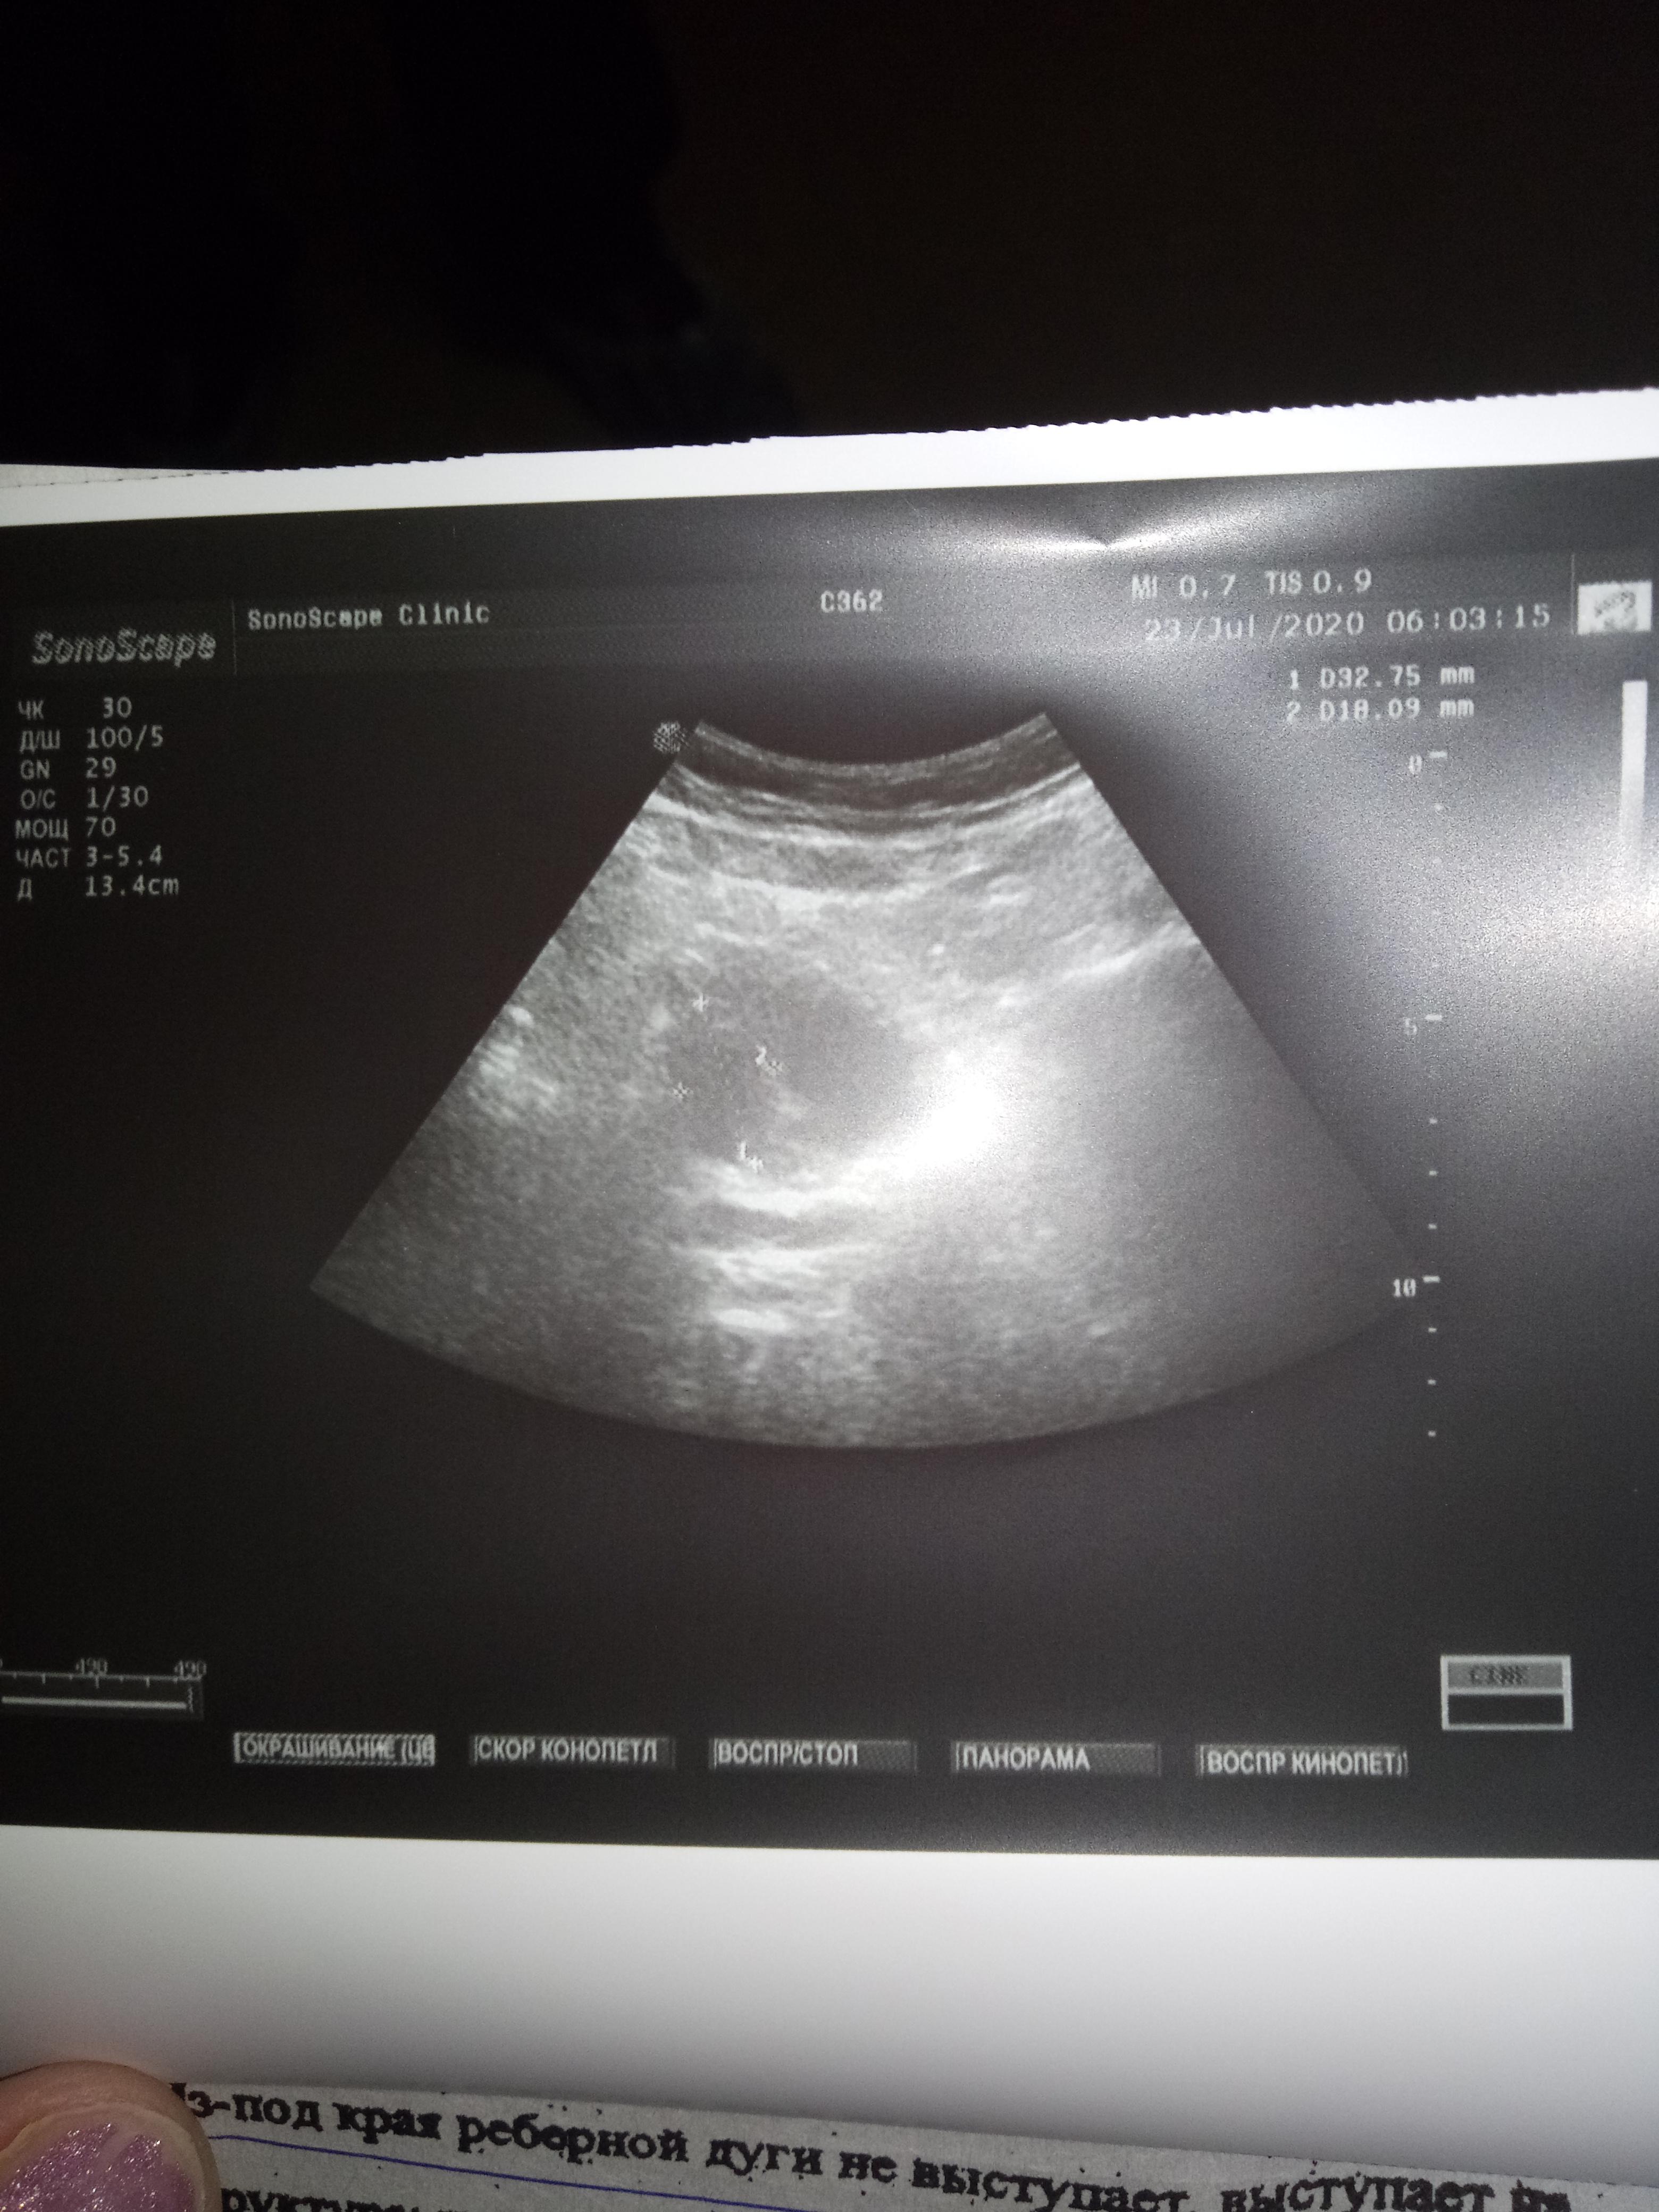

Пожалуйста,можно ли по данным анализам назначить лечение? Какая стадия рака?При отказе на операцию возможен ли прогноз,продолжительность жизни?

анализы отца,пожалуйста подскажите лечение,госпитализироваться отец отказался,боиться.Пожалуйста подскажите лечение,возможно ли оно?

Ответ врача

Здравствуйте! Безусловно, надо обратиться к онкоурологу, как минимум, необходима верификация диагноза и уточнение степени распространения процесса для определения тактики лечения и возможности применения малоинвазивных методов лечения. Берегите себя. Удачи!